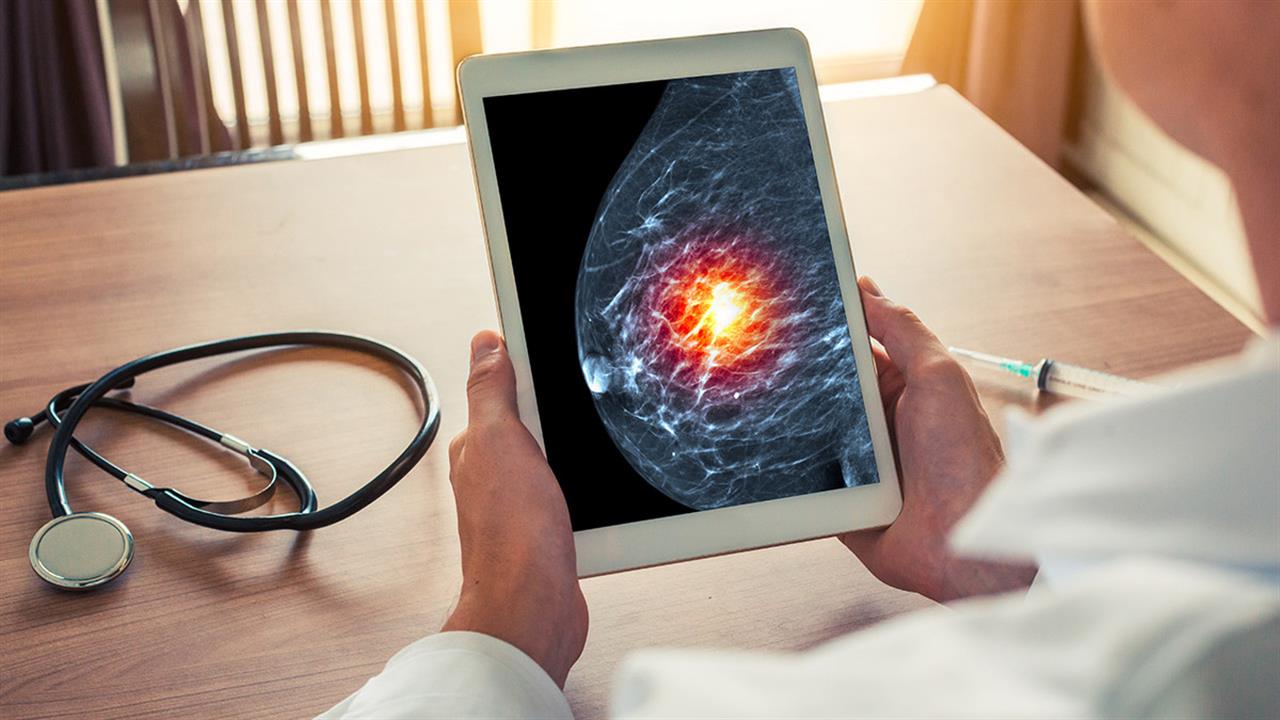

Η ψηφιακή μαστογραφία είναι αναμφίβολα ένα από τα μεγάλα όπλα μας στη μάχη κατά του καρκίνου του μαστού. Από τα τέλη της δεκαετίας του ΄60, όταν πρωτοξεκίνησε στην Νέα Υόρκη η καμπάνια της αναλογικής τότε μαστογραφίας, έως σήμερα, με τις νεώτερες εξελιγμένες τεχνικές ψηφιακής μαστογραφίας και ψηφιακής τομοσύνθεσης, η μείωση της θνητότητας από καρκίνο μαστού υπήρξε θεαματική, με μελέτες να την υπολογίζουν έως και 35%.

Η ψηφιακή μαστογραφία βέβαια είναι μορφολογική εξέταση, δηλαδή μας δίνει πληροφορίες καταρχάς για το αν υπάρχει κάποια αλλοίωση στο εσωτερικό του μαστού και εν συνεχεία μας δίνει πληροφορίες για το σχήμα, το μέγεθος και το περίγραμμα της αλλοίωσης.

Εξ΄ορισμού στη μαστογραφία δεν μπορούμε (ή μάλλον δεν μπορούσαμε έως τώρα) να λάβουμε πληροφορίες για την αγγείωση των απεικονιζόμενων αλλοιώσεων, παράμετρο πολύ σημαντική για τον χαρακτηρισμό τους. Κατεξοχήν αυτές οι συνδυαστικές πληροφορίες μορφολογίας και αγγείωσης των αλλοιώσεων του μαστού παρέχονται από την μαγνητική μαστογραφία, εξέταση όμως πιο χρονοβόρα, κοστοβόρα και όχι πάντα εύκολα διαθέσιμη.

Η ιδέα και εφαρμογή χρήσης σκιαγραφικού στη ψηφιακή μαστογραφία άλλαξε σχεδόν με επαναστατικό τρόπο το βλέμμα όλων ημών των εξειδικευμένων ακτινοδιαγνωστών μαστού ανά τον πλανήτη. Η τεχνική βασίζεται σε μια απλή έγχυση ιωδιούχου σκιαγραφικού από μια περιφερική φλέβα, κατά τον ίδιο τρόπο όπως για μια απλή αξονική τομογραφία.

Η ασθενής τοποθετείται στο μηχάνημα του μαστογράφου κατά τον ίδιο ακριβώς τρόπο όπως και για μία απλή ψηφιακή μαστογραφία. Εν συνεχεία λαμβάνονται εικόνες μετά την έγχυση του σκιαγραφικού σε συγκεκριμένες χρονικές στιγμές που μας επιτρέπουν την εκτίμηση και ανάλυση της αγγείωσης τόσο του φυσιολογικού μαστού όσο και τυχόν υποκείμενων αλλοιώσεων αυτού. Έτσι, έχουμε πλέον πρόσβαση και σε δυναμικές πληροφορίες που συμπληρώνουν ιδανικά τις μορφολογικές πληροφορίες και ενισχύουν την διαγνωστική μας ακρίβεια.

Η ψηφιακή μαστογραφία με έγχυση σκιαγραφικού χρησιμοποιείται για να δώσει απάντηση σε συγκεκριμένα και συχνά κλινικά ερωτήματα που αφορούν στον περαιτέρω χαρακτηρισμό αλλοιώσεων που αναδεικνύονται στη ψηφιακή μαστογραφία, όπως στην τοπική σταδιοποίηση σε πρωτοδιάγνωση κακοήθειας στο μαστό, στην εκτίμηση ανταπόκρισης στην προεγχειρητική θεραπεία, στον προσυμπτωματικό έλεγχο γυναικών με προφίλ υψηλού ρίσκου που έχουν αντένδειξη διενέργειας μαγνητικής μαστογραφίας ενώ υπάρχουν μελέτες που αξιολογούν την εν λόγω τεχνική για τον έλεγχο των αυξημένης πυκνότητας μαστών.

Στις μέχρι σήμερα πολυκεντρικές μελέτες, η ψηφιακή μαστογραφία με σκιαγραφικό αναδεικνύεται ως έχουσα μεγαλύτερη διαγνωστική ευαισθησία από την μαστογραφία και κατά περίπτωση μεγαλύτερη διαγνωστική ακρίβεια απ΄ ότι ο συνδυασμός μαστογραφίας και υπερηχογραφήματος. Αποτελεί, λοιπόν πλέον, άλλο ένα εργαλείο λίαν χρήσιμο και πολλά υποσχόμενο σε συγκεκριμένες κλινικές ενδείξεις όπως αναφέρθηκαν παραπάνω, που έρχεται να ενισχύσει τη διαγνωστική μας φαρέτρα στον απεικονιστικό έλεγχο του μαστού.